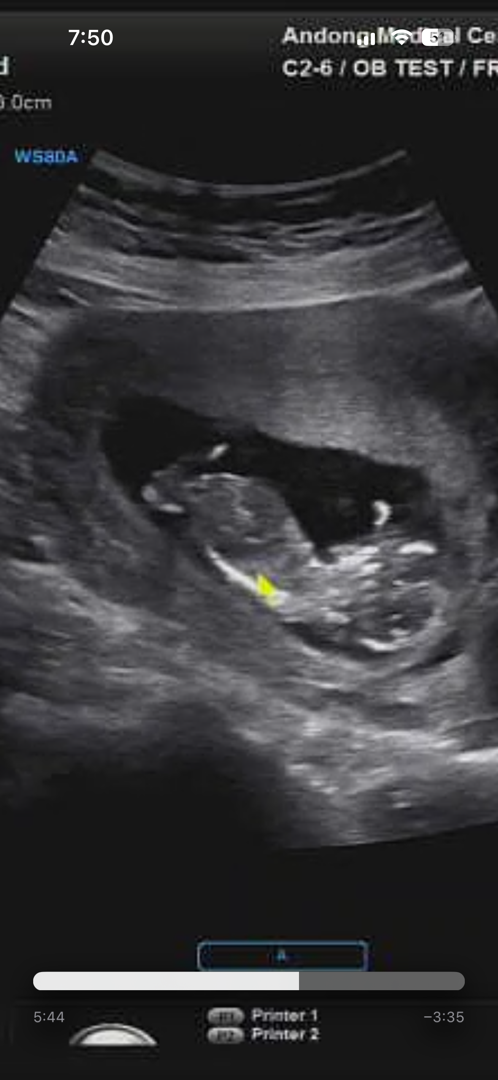

12주 1일 성별 각도법 봐주세용 ㅠㅠ

각도법 아무리 봐도ㅠ모르겠는데ㅠ 다리사이에 무언가 있는거같은데 12주엔 다?? 튀어나와있다고 하네요ㅠㅠ 저 사진만 보고 각도법으로 성별 예측할 수 있을 까용? 의견 마구 남겨주세요 :)